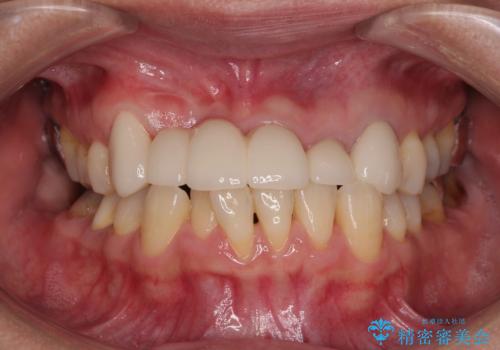

不具合の多い前歯 オールセラミックブリッジ治療

- 前歯のブリッジに違和感を感じるとのことで来院された患者様です。

受け口を無理やりブリッジで改善したことで、支台歯の1本は歯根が破折しており抜歯が必要な状態でした。

根管治療がされている歯の一部には根尖部の違和感があり、根管治療が必要と判断されました。

抜歯および根管治療を実施した後にオールセラミッククラウンにて補綴することとしました。

歯肉ラインの改善には歯周外科処置が必要でしたが、大きく笑っても歯肉ラインが唇に隠れるとのことで、外見の改善はせず、清掃性の大会ブリッジを装着いたしました。